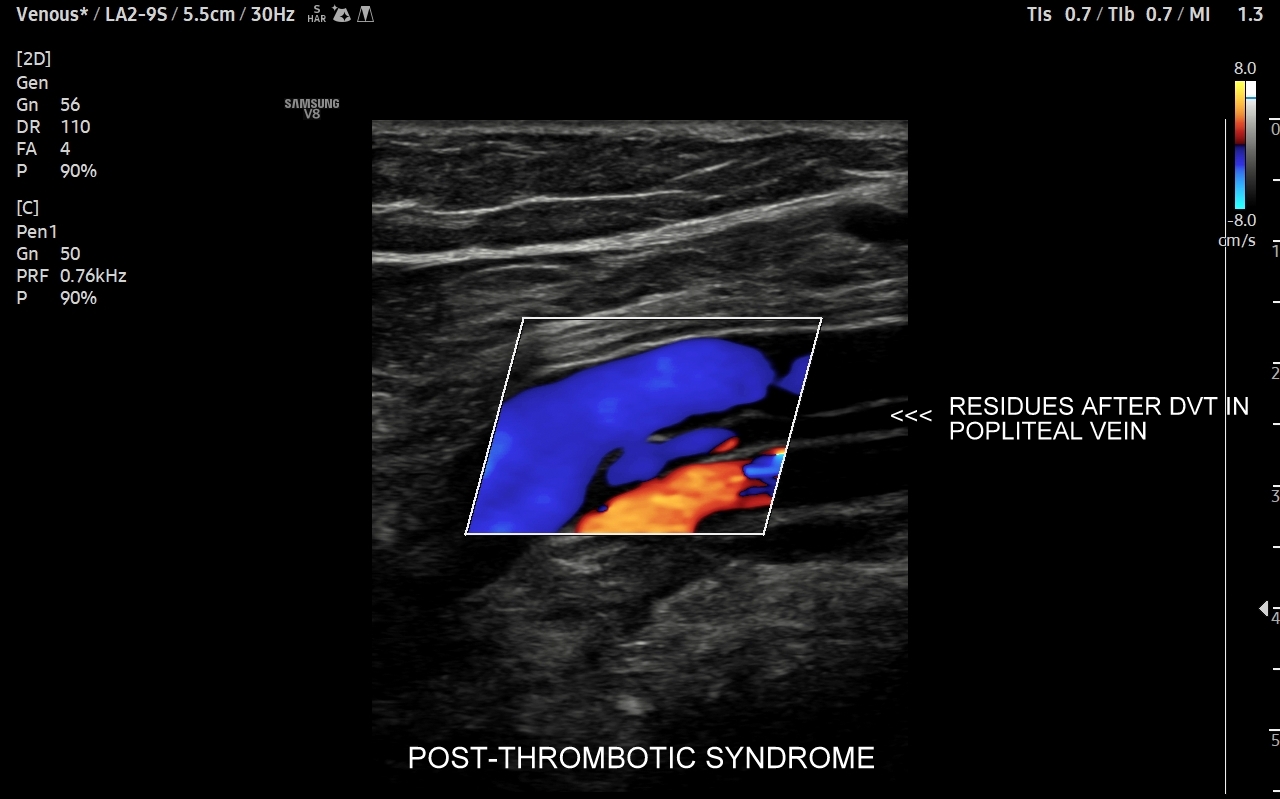

• zespół pozakrzepowy;

Czym jest zakrzepica żył? Zakrzepica żylna polega na powstaniu skrzepu wewnątrz naczynia żylnego i wtórnym rozwoju stanu zapalnego w okolicy naczynia. Choroba dotyczyć może układu powierzchownego żył lub żylaków, a w tym wypadku nie jest zwykle stanem niebezpiecznym; a także układu głębokiego żył, co z kolei jest stanem potencjalnie zagrażającym życiu, gdyż może sprowokować zatorowość płucną. Zakrzepica żył głębokich (ang. deep venous thrombosis DVT) częściej występuje w obrębie żył kończyn dolnych, następnie w obrębie żył biodrowych, rzadziej w żyle podobojczykowej i żyłach głębokich kończyny górnej. Przyczyny zakrzepicy żylnej są różnorodne i obejmują m. in. długie podróże, długotrwałe unieruchomienie, operacje ortopedyczne, chirurgiczne i szczękowe, urazy tkanek miękkich oraz złamania kości, genetycznie uwarunkowane trombofilie, nowotwory złośliwe, odwodnienie, infekcje miejscowe i ogólnoustrojowe. W przypadku zakrzepicy żyły podobojczykowej klasyczną jej przyczyną jest ucisk; w swojej praktyce klinicznej dr Szczepański spotkał się z zakrzepicą podobojczykową wywołaną m. in. przez ciężki plecak, wyciskanie sztangi na siłowni, czy przez uprawianie wspinaczki skałkowej. W warunkach szpitalnych zakrzepica żyły podobojczykowej lub żyły szyjnej wewnętrznej może pojawić się w wyniku zakładania cewników dożylnych. Sprawne wykrycie zakrzepicy w badaniu USG, a następnie wdrożenie odpowiedniej terapii uchronić może pacjenta przed powikłaniami ostrymi (np. zator płucny), jak i opóźnionymi (np. zespół pozakrzepowy).

Badanie USG żył kończyn dolnych najczęściej wykonywane jest w ramach diagnostyki niewydolności żył powierzchownych oraz ich objawów w postaci pajączków żylnych, żylaków kończyn dolnych, obrzęków i owrzodzeń żylnych. Kolejnym pod względem częstości wskazaniem do badania Doppler żył jest podejrzenie zakrzepicy żył głębokich kończyn dolnych, monitorowanie leczenia zakrzepicy oraz ocena jej powikłań odległych. Powikłaniem nieleczonej zakrzepicy żył głębokich może być zespół pozakrzepowy manifestujący się masywnymi obrzękami kończyny i zaburzeniami troficznymi. Badanie USG Doppler żył kończyn dolnych często uzupełniane jest oceną układu żył centralnych w miednicy i jamie brzusznej. W tych obszarach również pojawiać się mogą żylne zmiany zakrzepowe, niedrożności żył, a nawet zmiany nowotworowe.